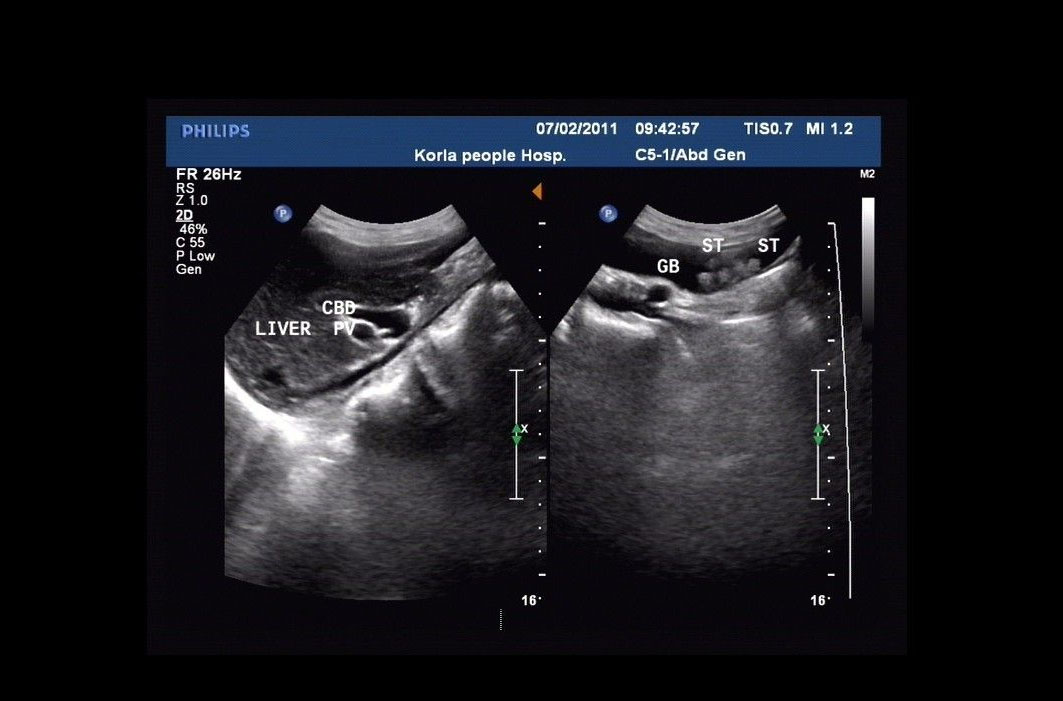

患膽結(jié)石需做超聲檢查

患膽結(jié)石需做超聲檢查,因需要了解結(jié)石的數(shù)量、形態(tài)、大小以及位置、膽囊管和頸部的變化,需要腹腔鏡手術(shù)的病例需要了解膽囊三角的相關(guān)變化;需要注意有無(wú)阻塞和并發(fā)癥,膽囊壁厚度變化,膽囊周圍變化,無(wú)聲影結(jié)石和膽囊占位的區(qū)別等等。老年人即便發(fā)生膽囊結(jié)石頸部或膽囊管嵌頓、膽囊炎化膿穿孔等改變,也會(huì)由于癥狀不典型、描述不確切、想挺挺就過(guò)去了而耽誤最佳和相對(duì)簡(jiǎn)單的治療期。